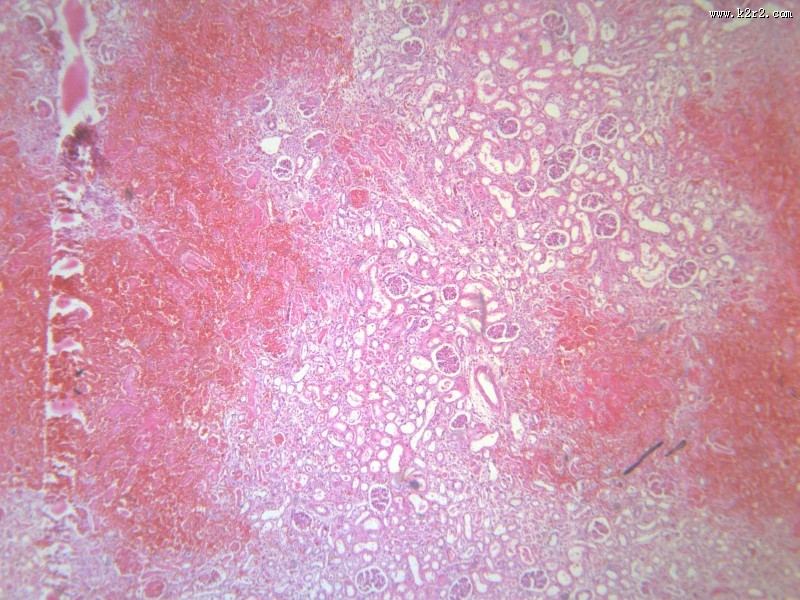

肾小管坏死 - 第1张

肾小管坏死

图集中 / 共有 12 张图片

肾凝固性坏死

肾小管水肿

医学

显微切片